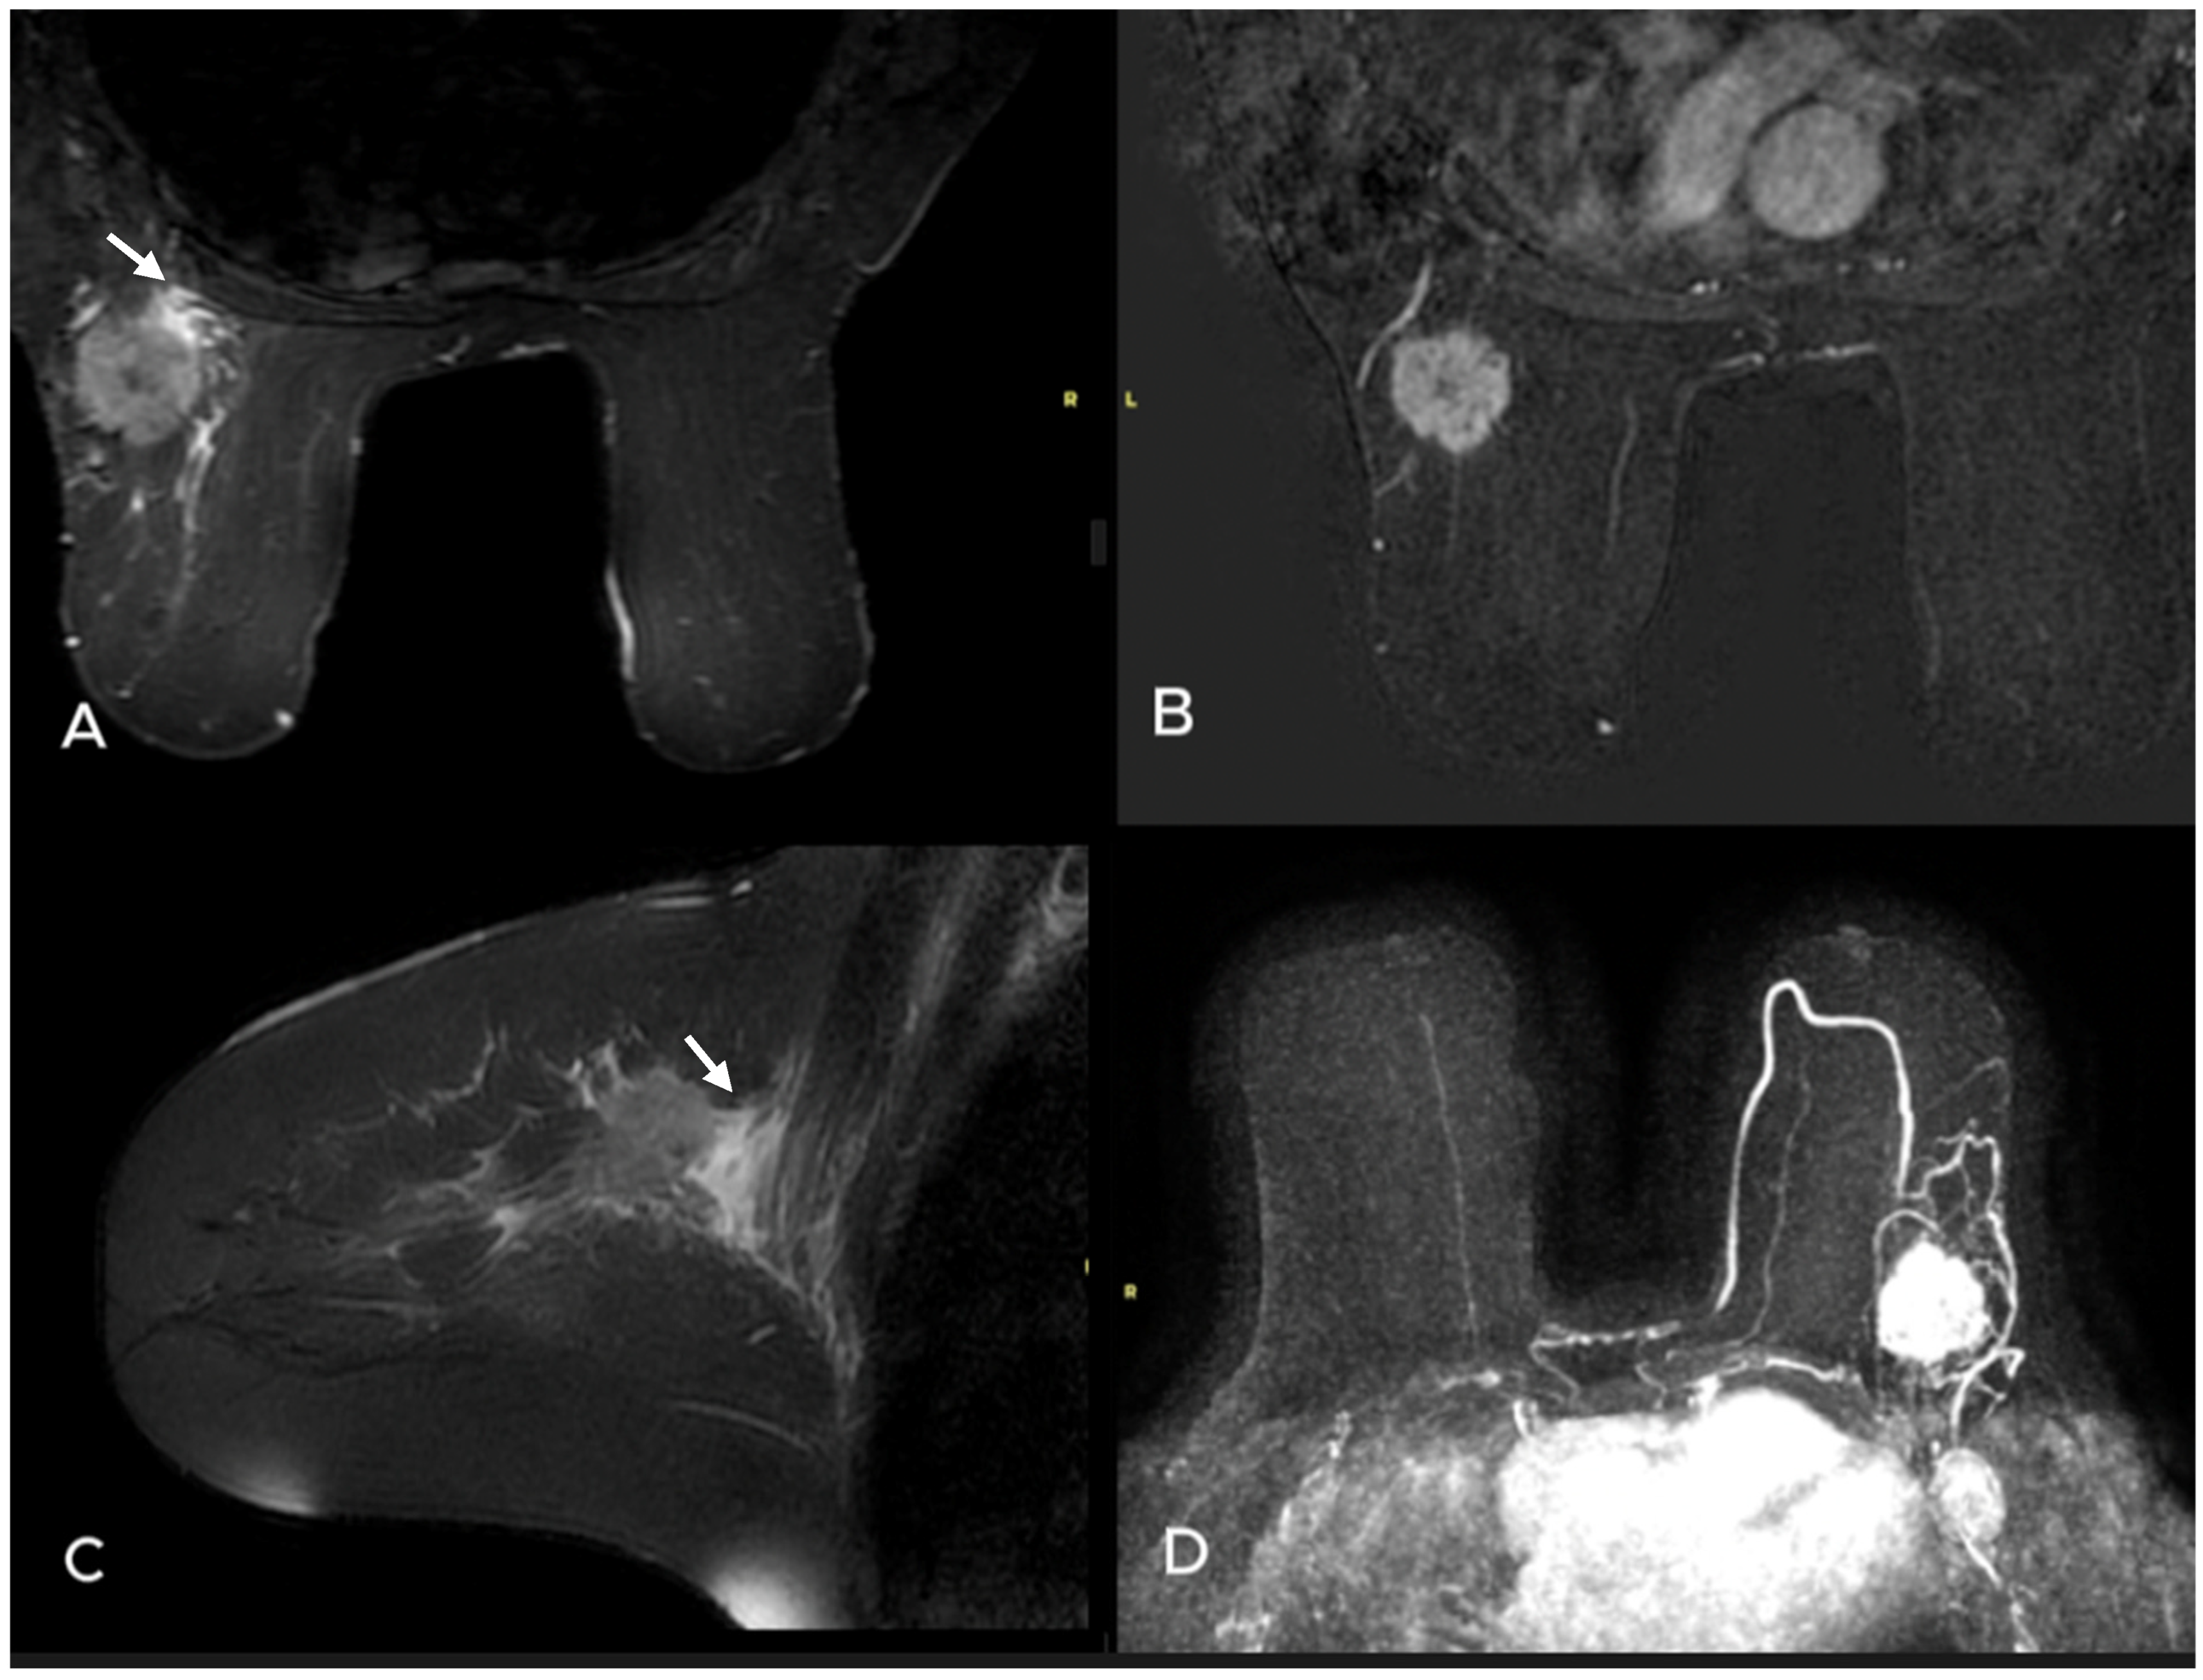

- Uematsu, T. Focal breast edema associated with malignancy on T2-weighted images of breast MRI: Peritumoral edema, prepectoral edema, and subcutaneous edema. Breast Cancer 2015, 22, 66–70. [Google Scholar] [CrossRef]

- Akdoğan Gemici, A.; Tokgoz Ozal, S.; Hocaoğlu, E.; Arslan, G.; Sen, E.; Altınay, S.; İnci, E. Relation of peritumoral, prepectoral and diffuse edema with histopathologic findings of breast cancer in preoperative 3T magnetic resonance imaging. J. Surg. Med. 2019, 3, 49–53. [Google Scholar]